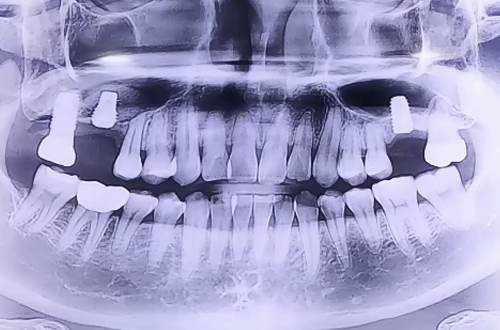

BEFORE

상악동거상술을 동반한 뼈이식 임플란트로 추정되는 부분에 염증이 생기면서 반대편에 임플란트를 진행하기 위해 방문하신 환자분이십니다.

반대편 오른쪽 위에도 뼈가 조금 남아있는 상태였기 때문에 상악동거상술을 동반하여 뼈이식을 진행해 드렸습니다.

뼈이식 이후 임플란트까지 당일 식립해 드렸으며 뼈이식의 양이 많기 때문에 뼈들이 단단해지는 기간인 6개월 이상 충분히 기다린 뒤에 큰 어금니 모양의 이를 제작해 드릴 예정입니다.